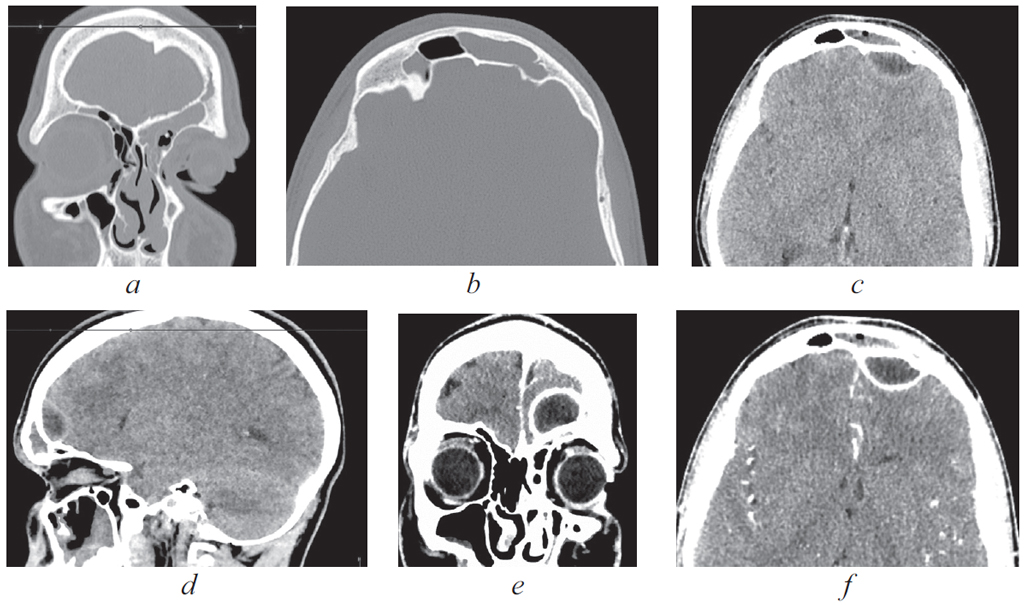

Риногенные внутричерепные осложнения, такие как абсцесс головного мозга и тромбоз вен и синусов головного мозга, по сей день остаются грозной, жизнеугрожающей патологией, не редко заканчивающейся летальным исходом, несмотря на широкое развитие антибактериальной терапии и приверженность пациентов к проводимому лечению. Нередко причиной развития внутричерепных осложнений служит обострение хронического воспалительного процесса в придаточных пазухах носа, тогда как острая ЛОР-патология синусов приводит к развитию риногенных осложнений лишь в небольшом проценте случаев. К сожалению, высокое развитие лучевой и лабораторной диагностики не всегда позволяет вовремя диагностировать данные состояния и оказать адекватную хирургическую помощь. В детском и подростковом возрасте важно выполнить своевременное полное и в то же время малоинвазивное, не приводящее к инвалидизации, хирургическое пособие. Анализ зарубежной литературы последних лет показывает, что нейрохирургические операции в различном объеме (от трепанопункции головного мозга до краниотомии) встречаются в подавляющем большинстве случаев лечения риногенных внутричерепных осложнений. В статье приводятся два клинических случая успешно пролеченных в отделении оториноларингологии Санкт-Петербургского государственного педиатрического медицинского университета пациентов с внутричерепными осложнениями без высокотравматичной нейрохирургической операции. Комбинация эндоназальной эндоскопической операции и массивной адекватной консервативной терапии (антибиотикотерапия в сочетании с применением антикоагулянтов при синус-тромбозе) позволяет добиться выздоровления пациента без обращения к нейрохирургическому вмешательству.